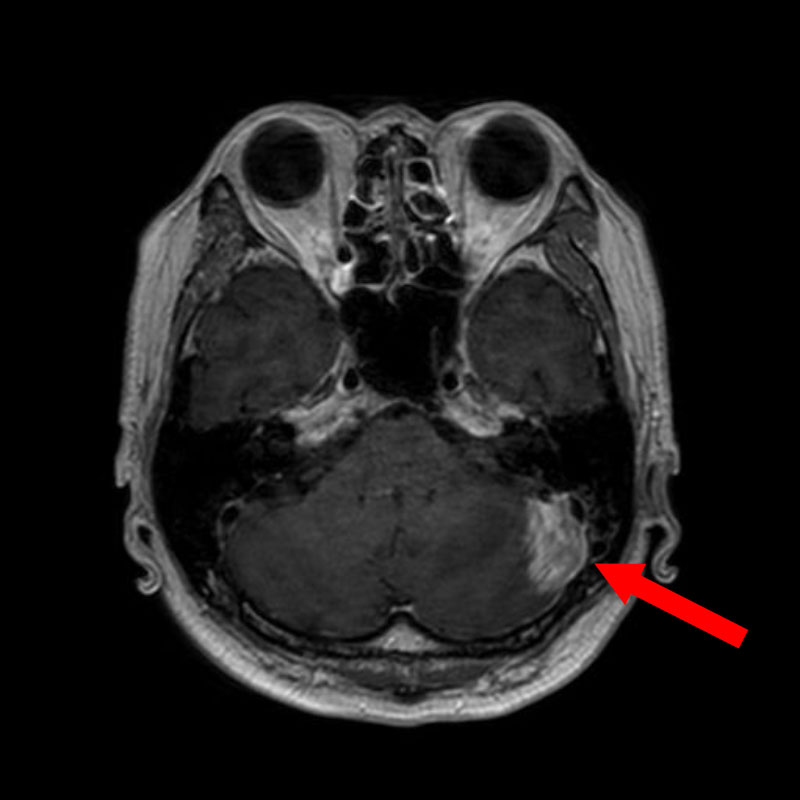

症例 '25年12月

No.

709

年_番号

手術年月

患者年齢

’25_111

'25年12月

60代

病名

術式

備考

左頭蓋窩腫瘤

頭蓋内腫瘍摘出術

断層撮影

手術前

1

手術前2

手術後